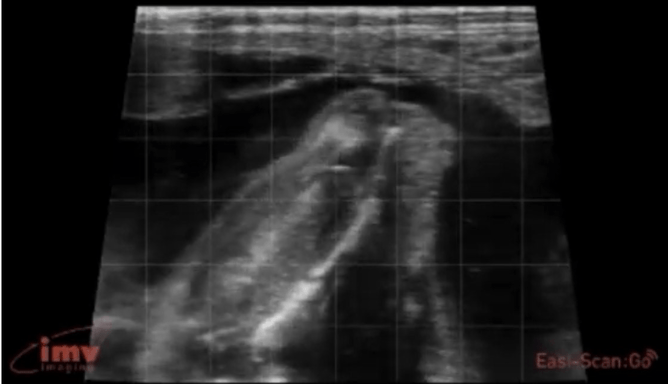

Our view of a calf foetus at various gestation stages: